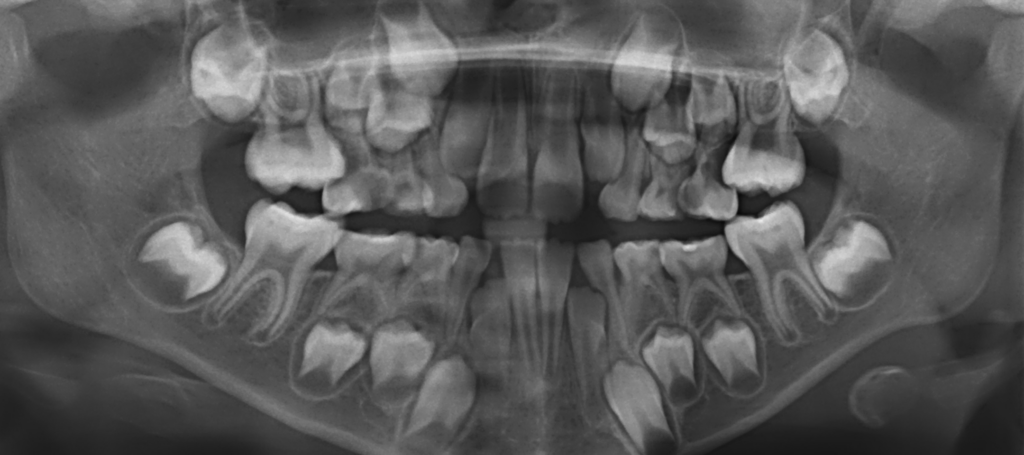

Ein Unfall als Chance?

Eine traumatische Zahnverletzung ist ein häufiger Befund in der Kinderzahnheilkunde. Es wird berichtet, dass mehr als eine Milliarde Menschen weltweit ein dentales Trauma erlebt haben.